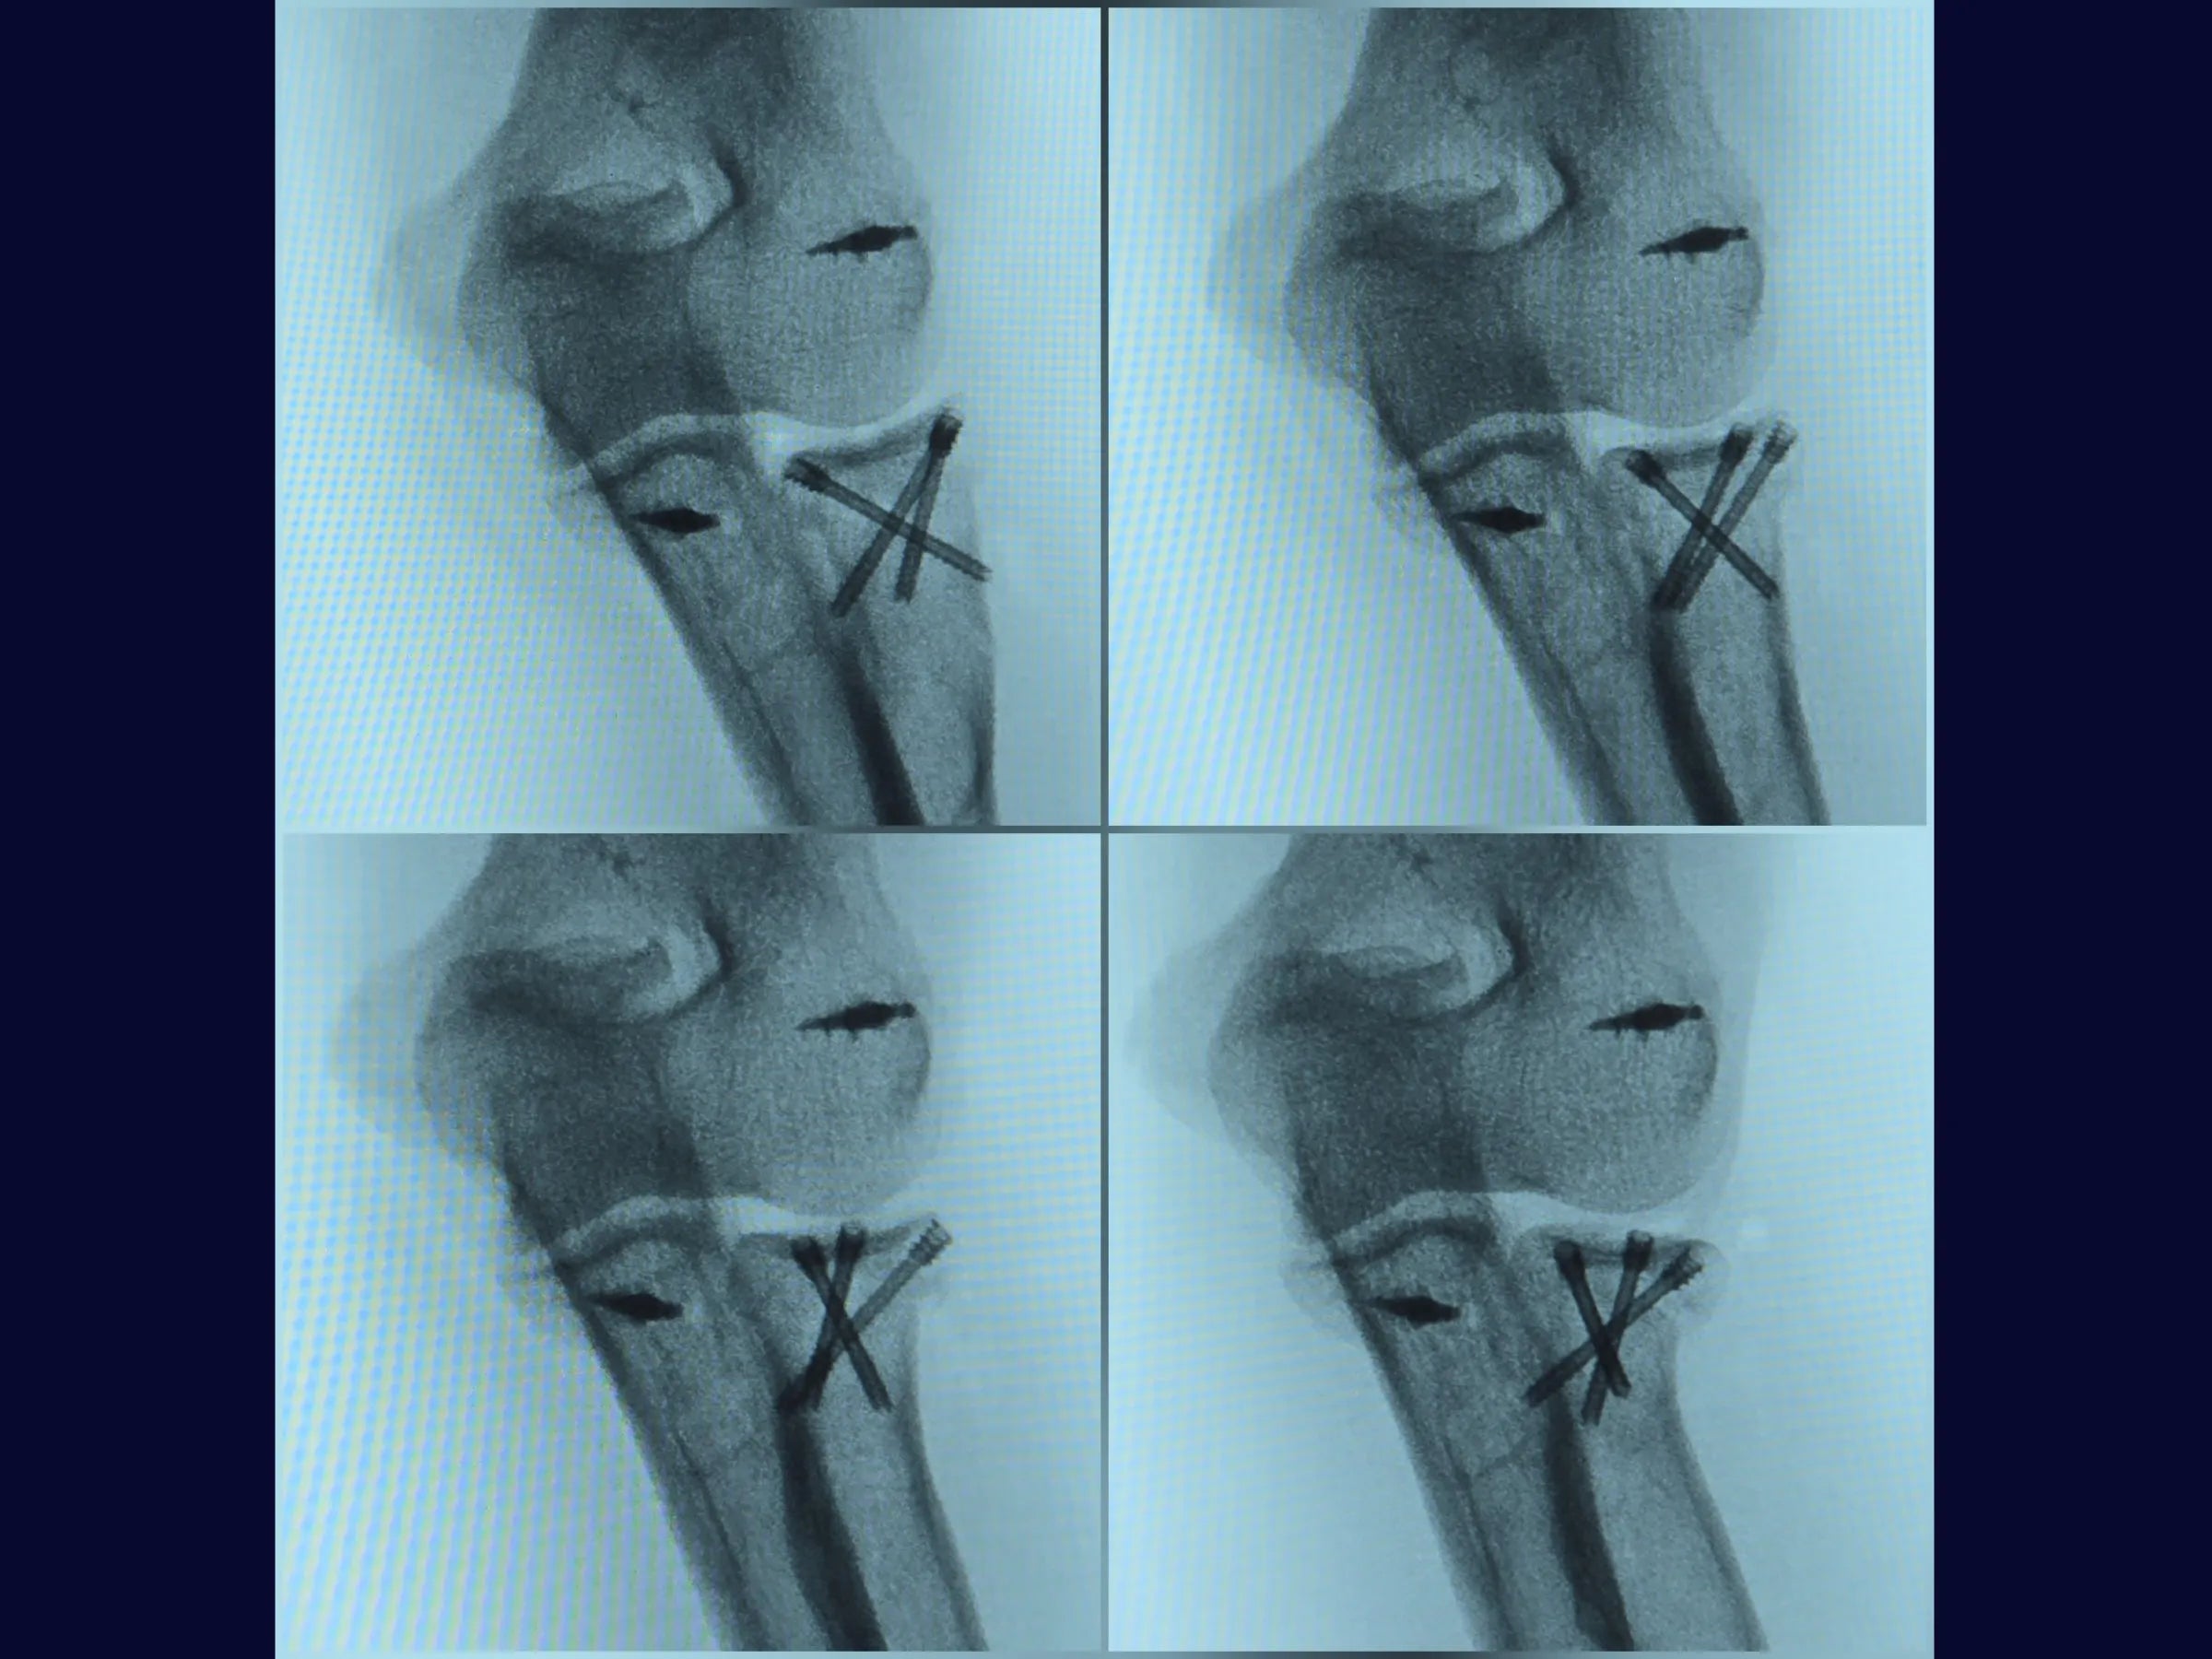

Este treinamento apresenta a técnica do tripé com parafusos de dupla compressão e reinserção capsular com âncora metálica, em vídeo 4K sob a perspectiva cirúrgica, permitindo compreender cada detalhe técnico e aplicar com segurança na prática.

- Técnica do tripé com parafusos de dupla compressão (2,4 mm).

- Testes de estabilidade intraoperatória e mobilidade precoce.

- Fixação Segura: Parafusos sepultados em ângulo biomecânico de 45°.